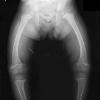

Rickets is a softening of bones in children potentially leading to fractures and deformity. Rickets is among the most frequent childhood diseases in many developing countries. The predominant cause is a vitamin D deficiency, but lack of adequate calcium in the diet may also lead to rickets (cases of severe diarrhea and vomiting may be the cause of the deficiency). Although it can occur in adults, the majority of cases occur in children suffering from severe malnutrition, usually resulting from famine or starvation during the early stages of childhood. Osteomalacia is the term used to describe a similar condition occurring in adults, generally due to a deficiency of vitamin D. The origin of the word "rickets" is probably from the Old English dialect word wrickken, to twist. The Greek derived word "rachitis" (???????, meaning "inflammation of the spine") was later adopted as the scientific term for rickets, due chiefly to the words similarity in sound.